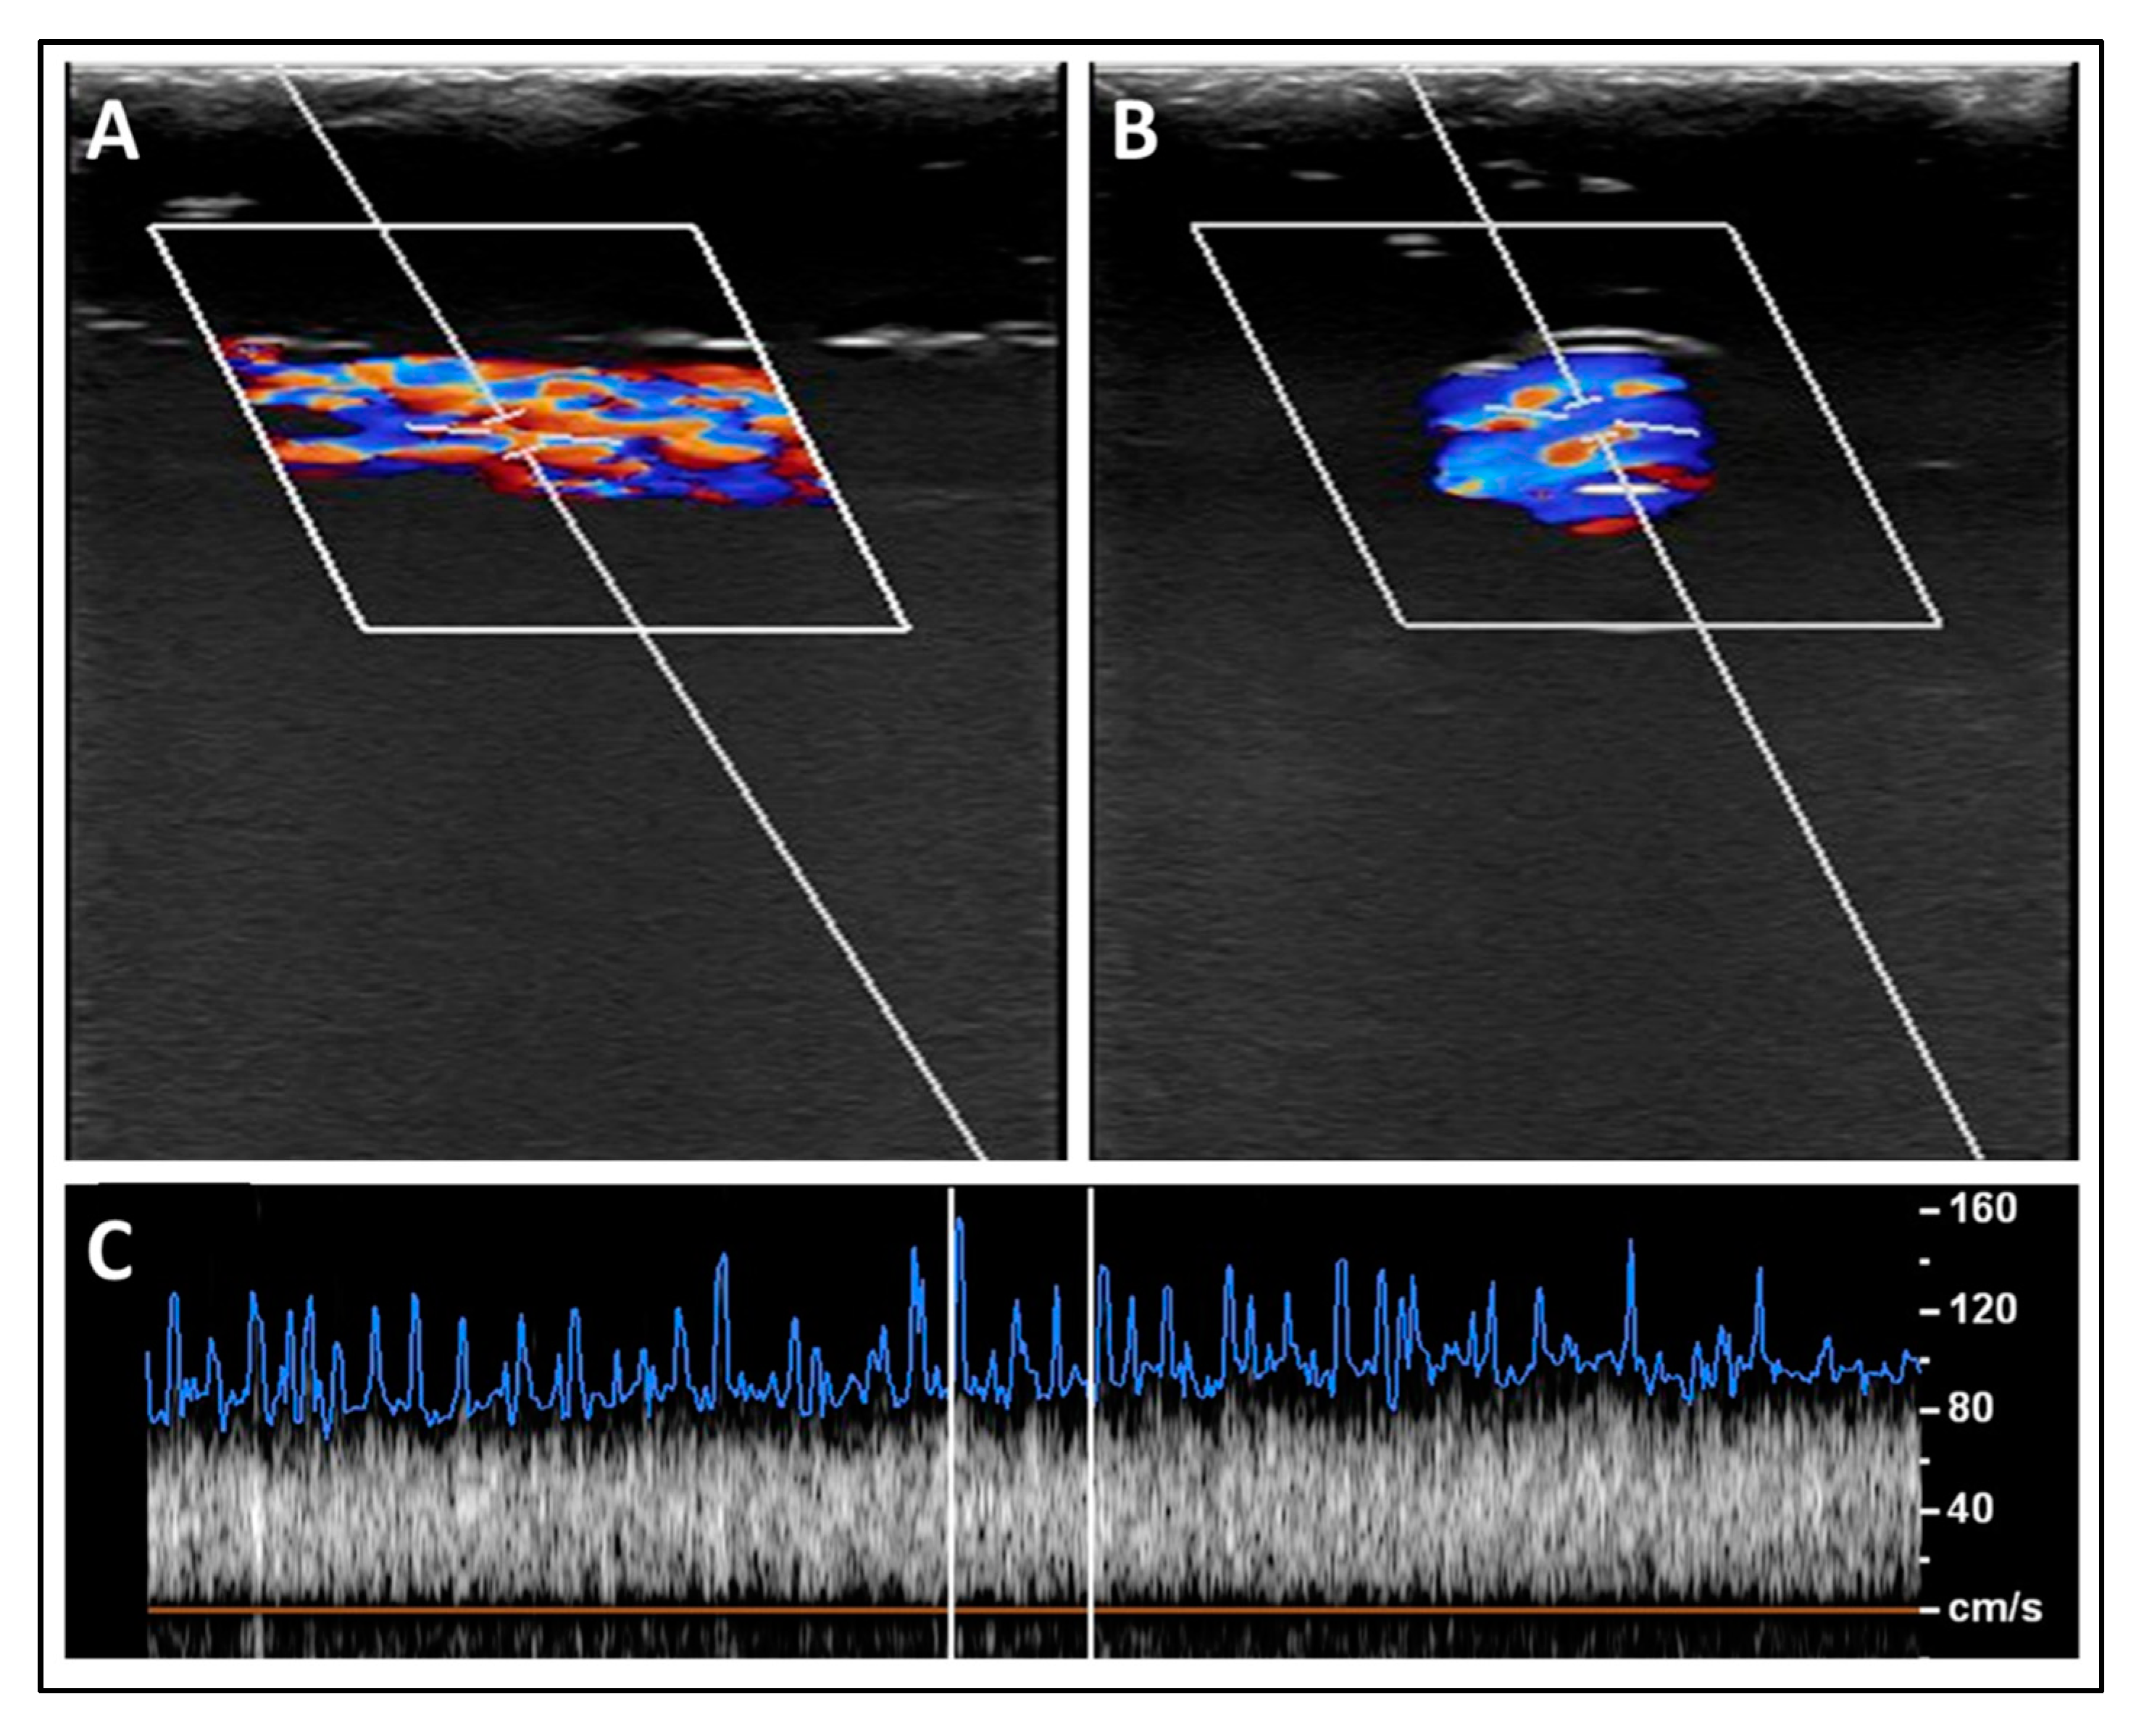

3.2. Experimental Validation of the Proposed Nanotechnology-Based Drug-Delivery System